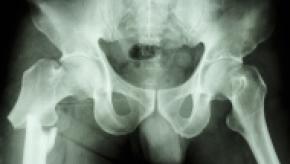

Osteoporosis treatment benefits people older than 80

People who are older than 80 should be considered for osteoporosis treatment after a fracture to avoid further risk, according to a study being presented Saturday at ENDO 2025, the Endocrine Society’s annual meeting in San Francisco, Calif.